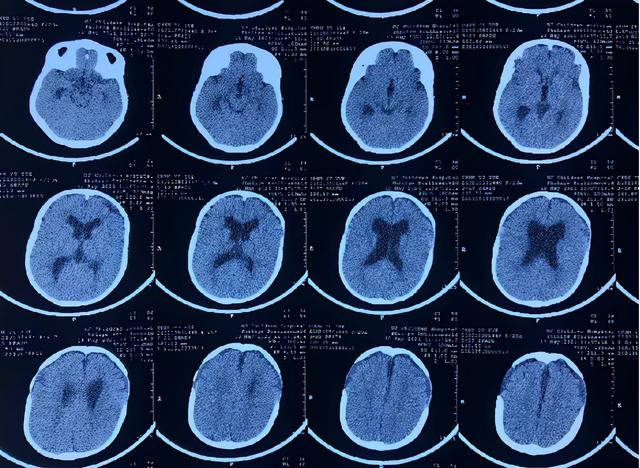

侧脑室扩大